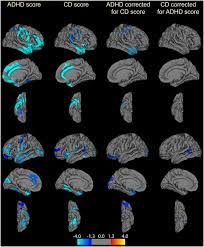

Secrets of your adhd brain. Adhd is a brain problem. Adhd brains smaller overall and in certain regions. Adhd brains have low levels of a neurotransmitter called norepinephrine. Attention deficit hyperactivity disorder (adhd) is a neurodevelopmental disorder characterized by inattention, or excessive activity and impulsivity, which are otherwise not appropriate for a person's age. Adhd brains are innovator brains. An adhd brain is a life sentence to never feeling in control. adhd brains are innovator brains. Attention deficit hyperactivity disorder (adhd) is a commonly misunderstood mental health condition. Overcoming adhd brain fog requires a heavy dose of willpower, energy and action. Of course, says edward hallowell, founder of the hallowell centers, which help treat people with adhd and other cognitive and emotional conditions in boston. The seconds tick by and you become more and more overwhelmed. An update on the controversies». Differences in the brain make it harder for people with adhd to work on a task unless they're really interested in it.

It's worth to post this multiple times, to convince lurkers that adhd is not a made up disease and to have some. But, it can be done. Previous studies have found links between differences in brain volume and adhd, but they were limited by small sample sizes. Certain brain structures related to emotion and reward are smaller in people with the disorder, new research finds. Adhd brains have low levels of a neurotransmitter called norepinephrine.

But the neurological underpinnings behind this. The seconds tick by and you become more and more overwhelmed. Adhd brains smaller overall and in certain regions. Attention deficit hyperactivity disorder (adhd) is a neurodevelopmental disorder characterized by inattention, or excessive activity and impulsivity, which are otherwise not appropriate for a person's age. Overcoming adhd brain fog requires a heavy dose of willpower, energy and action. Attention deficit hyperactivity disorder (adhd) is a neurodevelopmental disorder. Certain brain structures related to emotion and reward are smaller in people with the disorder, new research finds. Every brain, not just the adhd brain.

Certain brain structures related to emotion and reward are smaller in people with the disorder, new research finds.